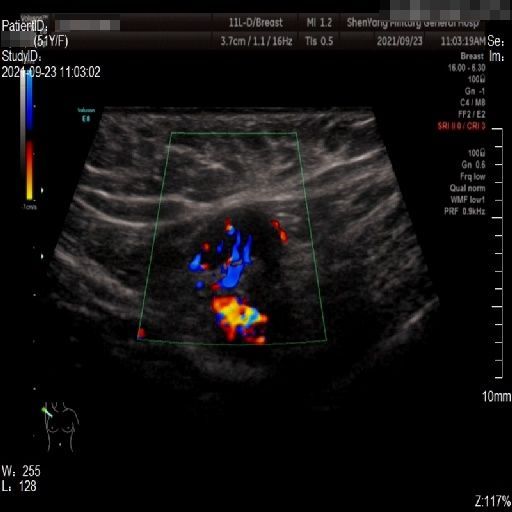

Images with certain annotations are considered noisy images in the context of the noise removal task, and corresponding images without these annotations are considered clean. Some typical images with various annotation are provided in Fig. 1.

In essence, a body marker annotation is a marker selected from a fixed set of icons that indicates different regions of the human body and its current orientation. It is typically located at the edge of the ultrasnoic image area and is labeled by the sonographer. On some ultrasound machines, the body marker annotation has a fixed position.

The radial line annotation is pairs of connected cross markers. They are usually placed at the edge of the lesion area, with its placement determined by the size of the lesion. One to three pairs of cross markers may be present in an image, corresponding to the three axes of 3D space, but typically there are only two pairs.

The vascular flow annotation is not an additional labeling feature meant to simplify identification. Rather, it serves as a bounding box that identifies the specific area of the image being examined by the ultrasound flowmeter. However, to keep things simple, we will continue to call it a form of annotation. The presence of this annotation indicates that the relevant examination has been conducted.

Refer to caption

(a)

(b)

(c)

Figure 1: Images with various annotations. (a) body marker annotation, (b) radical line annotation, (c) vascular flow annotation.